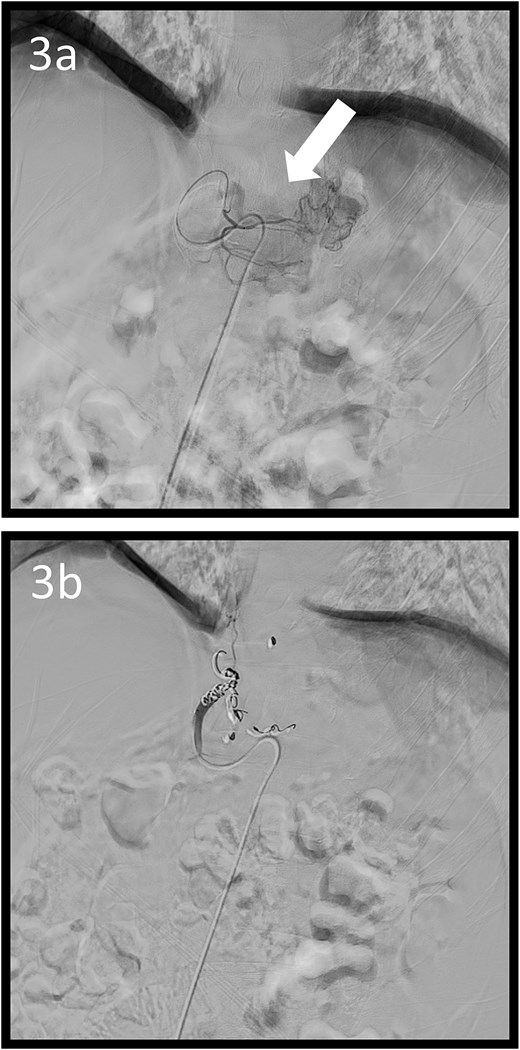

A 59-year-old man presented to the emergency department with loss of consciousness and hematemesis. His blood pressure was 90/50 mmHg. The patient’s haemoglobin level was 7.9 g/dL. The patient was haemodynamically unstable, and 12 units of red blood cell (RBC) concentrate were administered. Contrast-enhanced computed tomography (CT) revealed a gastric hyper-vascular mass on the lesser curvature (Fig. 1). Emergency upper gastrointestinal (GI) endoscopy performed under endotracheal intubation and ventilatory management revealed a large type 1 oozing tumour (Fig. 2a). Haemostatic procedures were not performed due to technical difficulties. Emergency angiography revealed a tumour stain from the left gastric artery, which was coil embolized (Fig. 3). Upper GI endoscopy 2 days later revealed no bleeding (Fig. 2b). After embolization, the patient became haemodynamically stable. It was later discovered that he had undergone open omental filling at another hospital 1 year prior due to GC perforation and left his disease untreated for a year at his own discretion. The patient received combination chemotherapy with S-1 and oxaliplatin, which was remarkably effective. Eight months after embolization, laparoscopic total gastrectomy with Roux-en-Y reconstruction and lymph node dissection were performed. The final histopathological diagnosis was T2N0M0 stage IB. Macroscopic findings revealed a type 1 tumour in the upper part of the stomach. Histopathological findings revealed that the tumour was a well-differentiated tubular adenocarcinoma. All surgical margins were negative. The patient had an uneventful postoperative course and was discharged 7 days after surgery. The patient was well, with no recurrence noted during the 35 months of follow-up.

Angiographic images; (a) the left gastric arteriography showing tumour staining (arrow); (b) the left gastric artery was coil embolized.